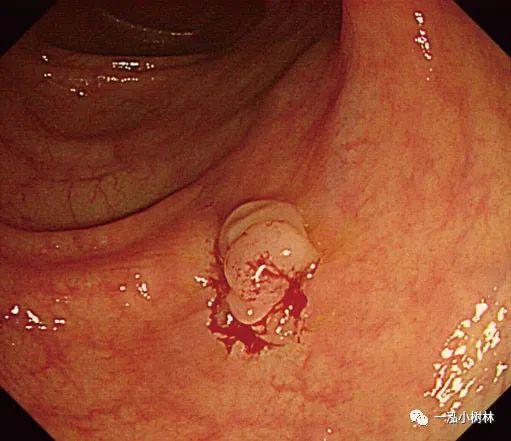

例1 标准活检钳冷钳息肉切除术示例

图1a 乙状结肠0-IIa型小腺瘤,大小2mm

图1b 冷钳息肉摘除术后黏膜出血